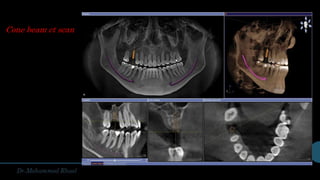

Radiographical

evaluation

Conventional imaging

Opg

occlusal

Periapical

Cephalometric

Cone beam ct scan